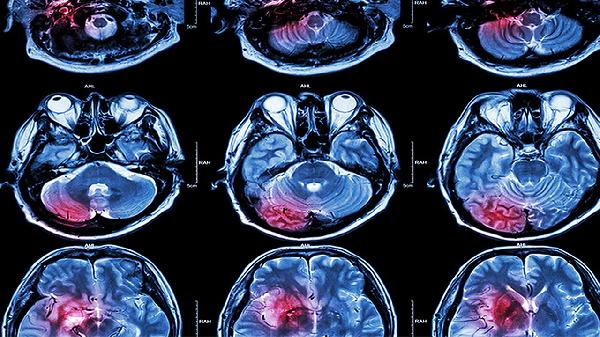

当患者存在脑血管病变、外伤或肿瘤等可能同时累及头颈部的疾病时,医生会建议联合扫描。例如突发剧烈头痛伴颈部僵直需排查蛛网膜下腔出血时,头颈联合CT能一次性评估颅内出血和血管痉挛情况。

现代多层螺旋CT扫描范围可达50厘米以上,单次扫描即可覆盖颅顶至胸廓入口。部分高端设备配备智能剂量调节系统,能自动优化不同部位的扫描参数,确保图像质量的同时减少辐射差异。